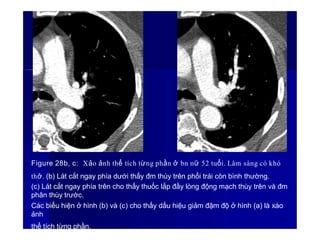

Figure 28b, c: Xảo ảnh thể tích từng phần ở bn nữ 52 tuổi. Lâm sàng có khó

thở. (b) Lát cắt ngay phía dưới thấy đm thùy trên phổi trái còn bình thường.

(c) Lát cắt ngay phía trên cho thấy thuốc lắp đầy lòng động mạch thùy trên và đm

phân thùy trước.

Các biểu hiện ở hình (b) và (c) cho thấy dấu hiệu giảm đậm độ ở hình (a) là xáo

ảnh

38

thể tích từng phần.